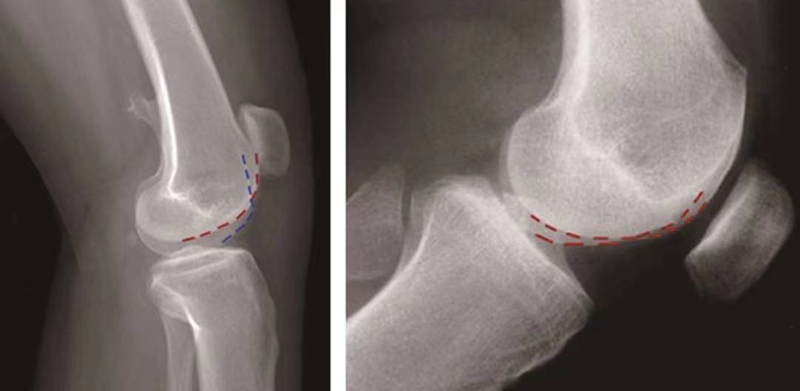

突起征:

H.Dejour在1996年提出突起征(spur或bump)或滑车近端突起征(supratrochlear spur),是指在膝关节标准侧位像上,股骨滑车沟基底线的最高点位于股骨前方皮质延长线的前方(图12)。这种征象的实质是股骨滑车近端的整体抬高。在膝关节屈曲早期,髌骨必须越过滑车近端的突起才能进入股骨滑车,因此,容易出现髌骨向外脱位。如果突起征>5mm即为异常,意味着股骨滑车基底高于股骨外髁的轮廓。

图12 突起征

双轨征(或称为双线征):

是指在膝关节标准侧位像上,代表股骨内外侧滑车的两条线分开,呈双轨样(图13)。它的出现提示股骨内侧滑车发育低平,导致它的前缘出现晚于外侧滑车。

图13 双轨征